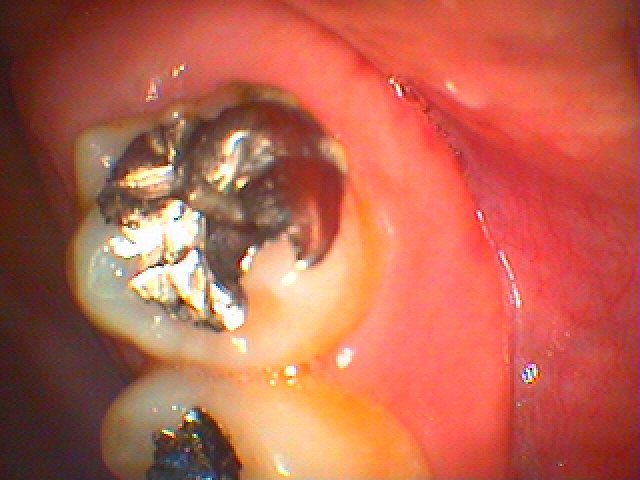

お知らせ|広島市安佐南区の歯科医院 > お知らせ トップ お知らせ・ブログ お知らせ スタッフブログ お知らせ お知らせ 2021/08/27 右下6番のインプラント埋入 50代後半男性 将来的に歯を何本か石なっているためにインプラントにてしっかりと噛めるようにしておきたい お知らせ 2021/08/27 右下7番の傾斜歯の被せを外して根管治療から、スペースを作り6番にインプラント埋入を行っていきます 50代後半男性 お知らせ 2021/08/26 右下4番の銀歯を外して白いセラミックによる審美治療 40代女性 矯正をされていた方になります お知らせ 2021/08/26 左上の7番を破折が原因で抜歯を行いました ここへインプラントを埋入していきます 40代後半男性 お知らせ 2021/08/26 左下奥歯の完全水平埋伏歯の難抜歯 40代男性 親知らずが原因で7番に虫歯ができていました お知らせ 2021/08/25 右上の完全埋伏歯の難抜歯 30代男性 いつも歯茎が腫れる お知らせ 2021/08/25 銀歯を外してセラミックを入れていきます 審美治療 40代女性 お知らせ 2021/08/25 左上の5番の銀歯の被せを白いセラミックへやり変えていきます 40代女性 お知らせ 2021/08/24 右上6番の被せを外して白いセラミックへやり変えていきます 40代女性 お知らせ 2021/08/24 右下6番のインプラント治療続き 2か月後、いよいよインプラント部に歯を立てていきます << 1 2 3 4 5 … 195 196 197 198 199 … 485 486 487 488 489 >> Web診療予約 初めての方へ 選ばれ続ける理由 院内設備について 歯が痛いしみる一般歯科 歯がぐらぐらする歯周病 健康な歯を保ちたい予防歯科 子供の虫歯予防をしたい小児歯科 銀歯をセラミックに審美歯科 白い歯を目指しませんか?ホワイトニング 矯正専門医がいるので安心矯正歯科 抜けた歯を補いたいインプラント・入れ歯 医院案内 スタッフ紹介 メリィハウス歯科クリニックオフィシャルホームページ ラベンダー歯科クリニックオフィシャルホームページ お知らせ・ブログ ホーム 診療科目 一般歯科 歯周病治療 予防治療 小児歯科 審美治療 ホワイトニング 矯正歯科 入れ歯・インプラント マウスピース矯正 初めての方へ 院長・スタッフ 設備紹介 医院案内・アクセス メニューを閉じる